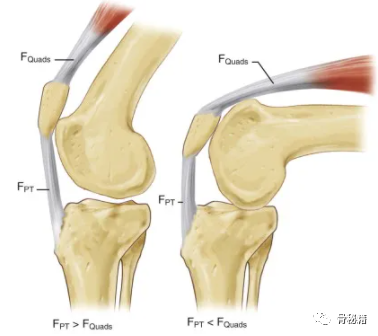

髌骨作为杠杆和垫片的机械功能,以增加髌腱力矩臂。

左图,当膝盖接近伸展位置时,与股四头肌收缩产生的力值( F Quads )相比,髌骨机构的杠杆作用在髌腱 ( F PT ) 中产生更大的力值。

右,膝关节处于屈曲位置,髌骨的杠杆作用减弱,髌腱产生的力值小于股四头肌产生的力值。